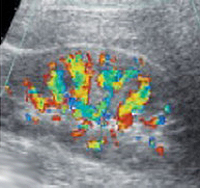

При проведении пробы Зимницкого выявляется изогипостенурия. УЗИ почек свидетельствует о снижении толщины паренхимы и уменьшении размера почек. Снижение внутриорганного и магистрального почечного кровотока выявляется на УЗДГ сосудов почек. Рентгенконтрастную урографию следует применять с осторожностью из-за нефротоксичности многих контрастных препаратов. Перечень других диагностических процедур определяется характером патологии, ставшей причиной развития ХПН.